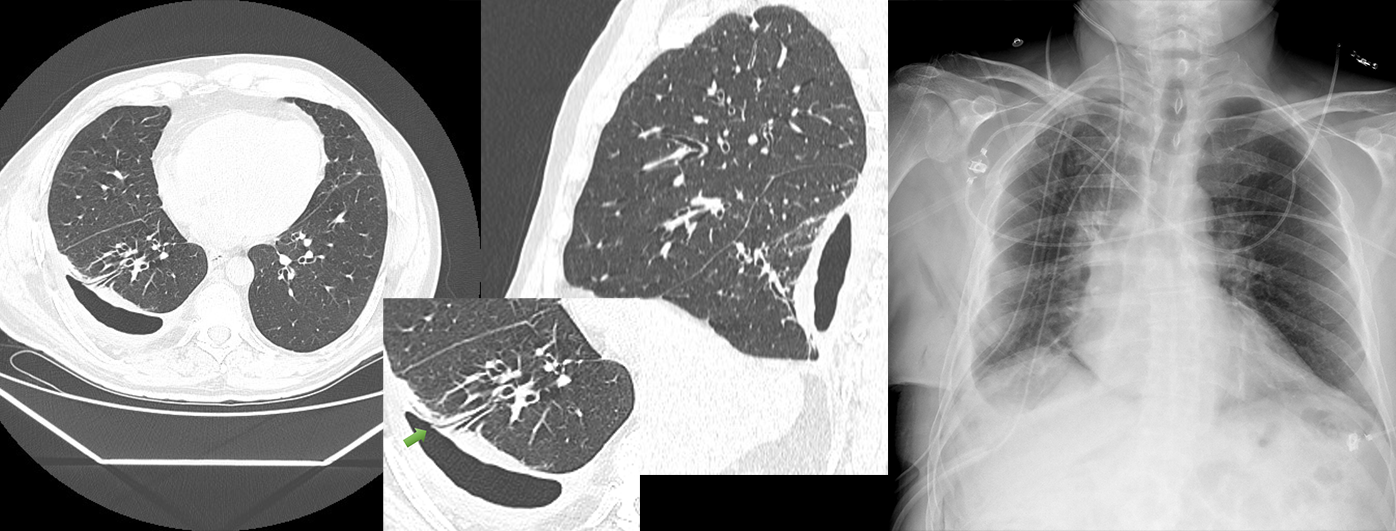

Вторая демонстрация: пациент с исходно инфильтративным туберкулезом верхней доли правого легкого, МБТ (+), ЛЧ МБТ, осложненным правосторонним специфическим плевритом. На фоне лечения с февраля 2020 в ПТД по месту жительства противотуберкулезными препаратами I ряда проводились многократные пункции плевральной полости без существенной положительной динамики.

В июле процесс осложнился правосторонним пиопневмотораксом, в связи с чем выполнено дренирование правой плевральной полости. На фоне неэффективной закрытой санации правой плевральной полости на дренаже исход заболевания - формирование правосторонней хронической смешанной эмпиемой плевры с бронхоплевральным свищом (ПБ9), ассоциированной с МБТ (+) ЛЧ МБТ и Pseudomonas aeruginosa. Больному выполнена нижняя лобэктомия справа с эпмиемэктомией.

КТ-картина осумкованной эмпиемы плевры справа, признаки бронхо-плеврального сообщения с ПБ9, посттуберкулезные изменения в верхушке правого легкого.

На сегодняшние сутки состояние пациента стабильное, по данным рентгенографии органов грудной клетки 29.10.2020 легкие представляются практически расправленными, свежей инфильтрации в легких не выявлено.